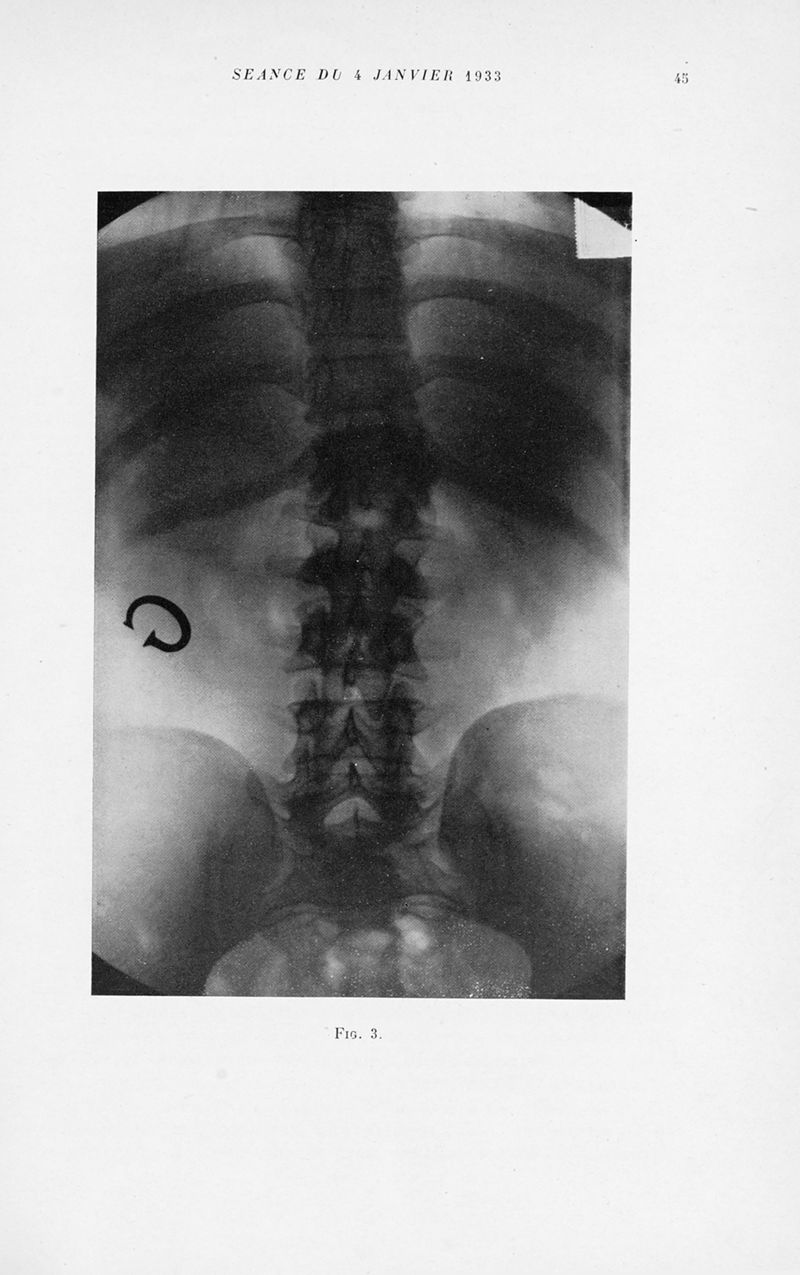

Bulletins et mémoires de la société nationale de chirurgie

Tome LIX, 1933. - Paris : Masson, 1933.